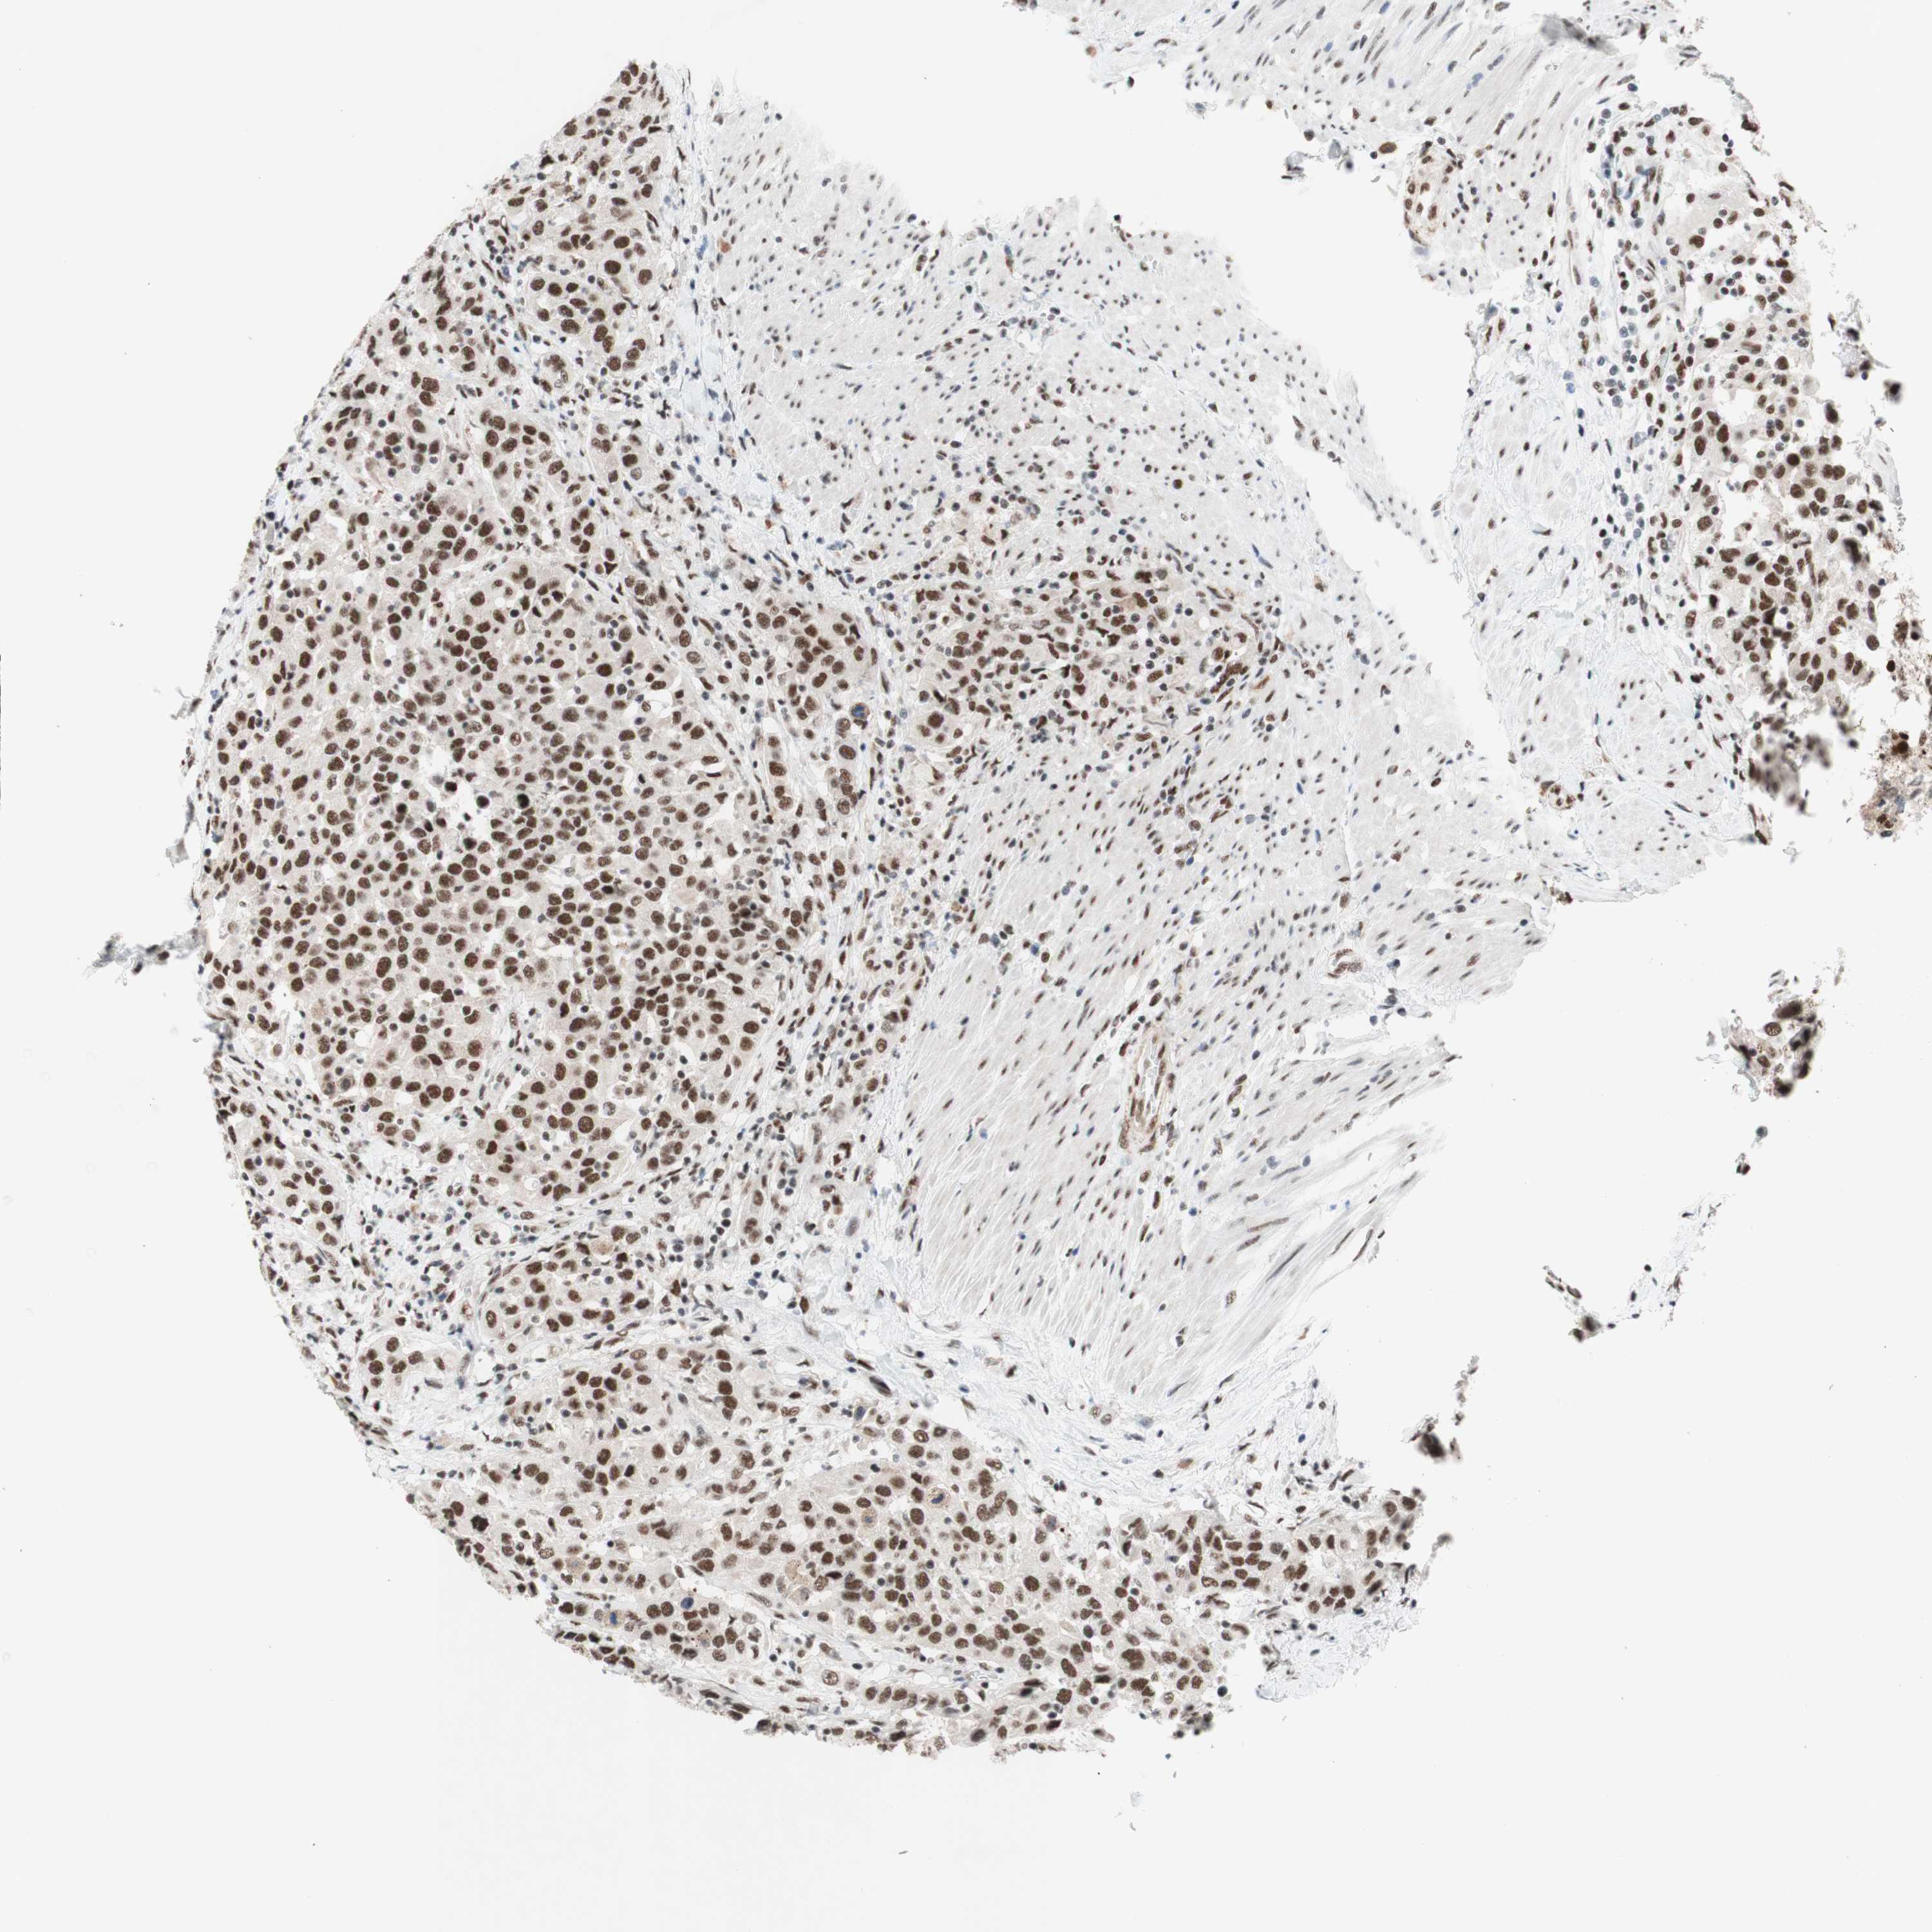

UROTHELIAL CANCER - Protein expressioni

A mouse-over function shows sample information and annotation data. Click on an image to view it in a full screen mode. Samples can be filtered based on level of antibody staining by selecting one or several of the following categories: high, medium, low and not detected. The assay and annotation is described here.

Note that samples used for immunohistochemistry by the Human Protein Atlas do not correspond to samples in the TCGA dataset.

Antibody stainingi

Antibody staining in the annotated cell types in the current human tissue is reported as not detected, low, medium, or high, based on conventional immunohistochemistry profiling in selected tissues. This score is based on the combination of the staining intensity and fraction of stained cells.

Each image is clickable and will lead to virtual microscopy that enables deeper exploration of all samples and also displays staining intensity scores, fraction scores and subcellular localization as well as patient and tissue information for each sample.

Antibody HPA038051

Antibody HPA059070

Antibody CAB012448

Staining

High

Medium

Low

Not detected

Intensity

Strong

Moderate

Weak

Negative

Quantity

>75%

75%-25%

<25%

None

Location

Nuclear

Cytoplasmic/membranous

Cytoplasmic/membranous,nuclear

Urothelial carcinoma, High grade

Urothelial carcinoma, Low grade

Urothelial carcinoma, NOS